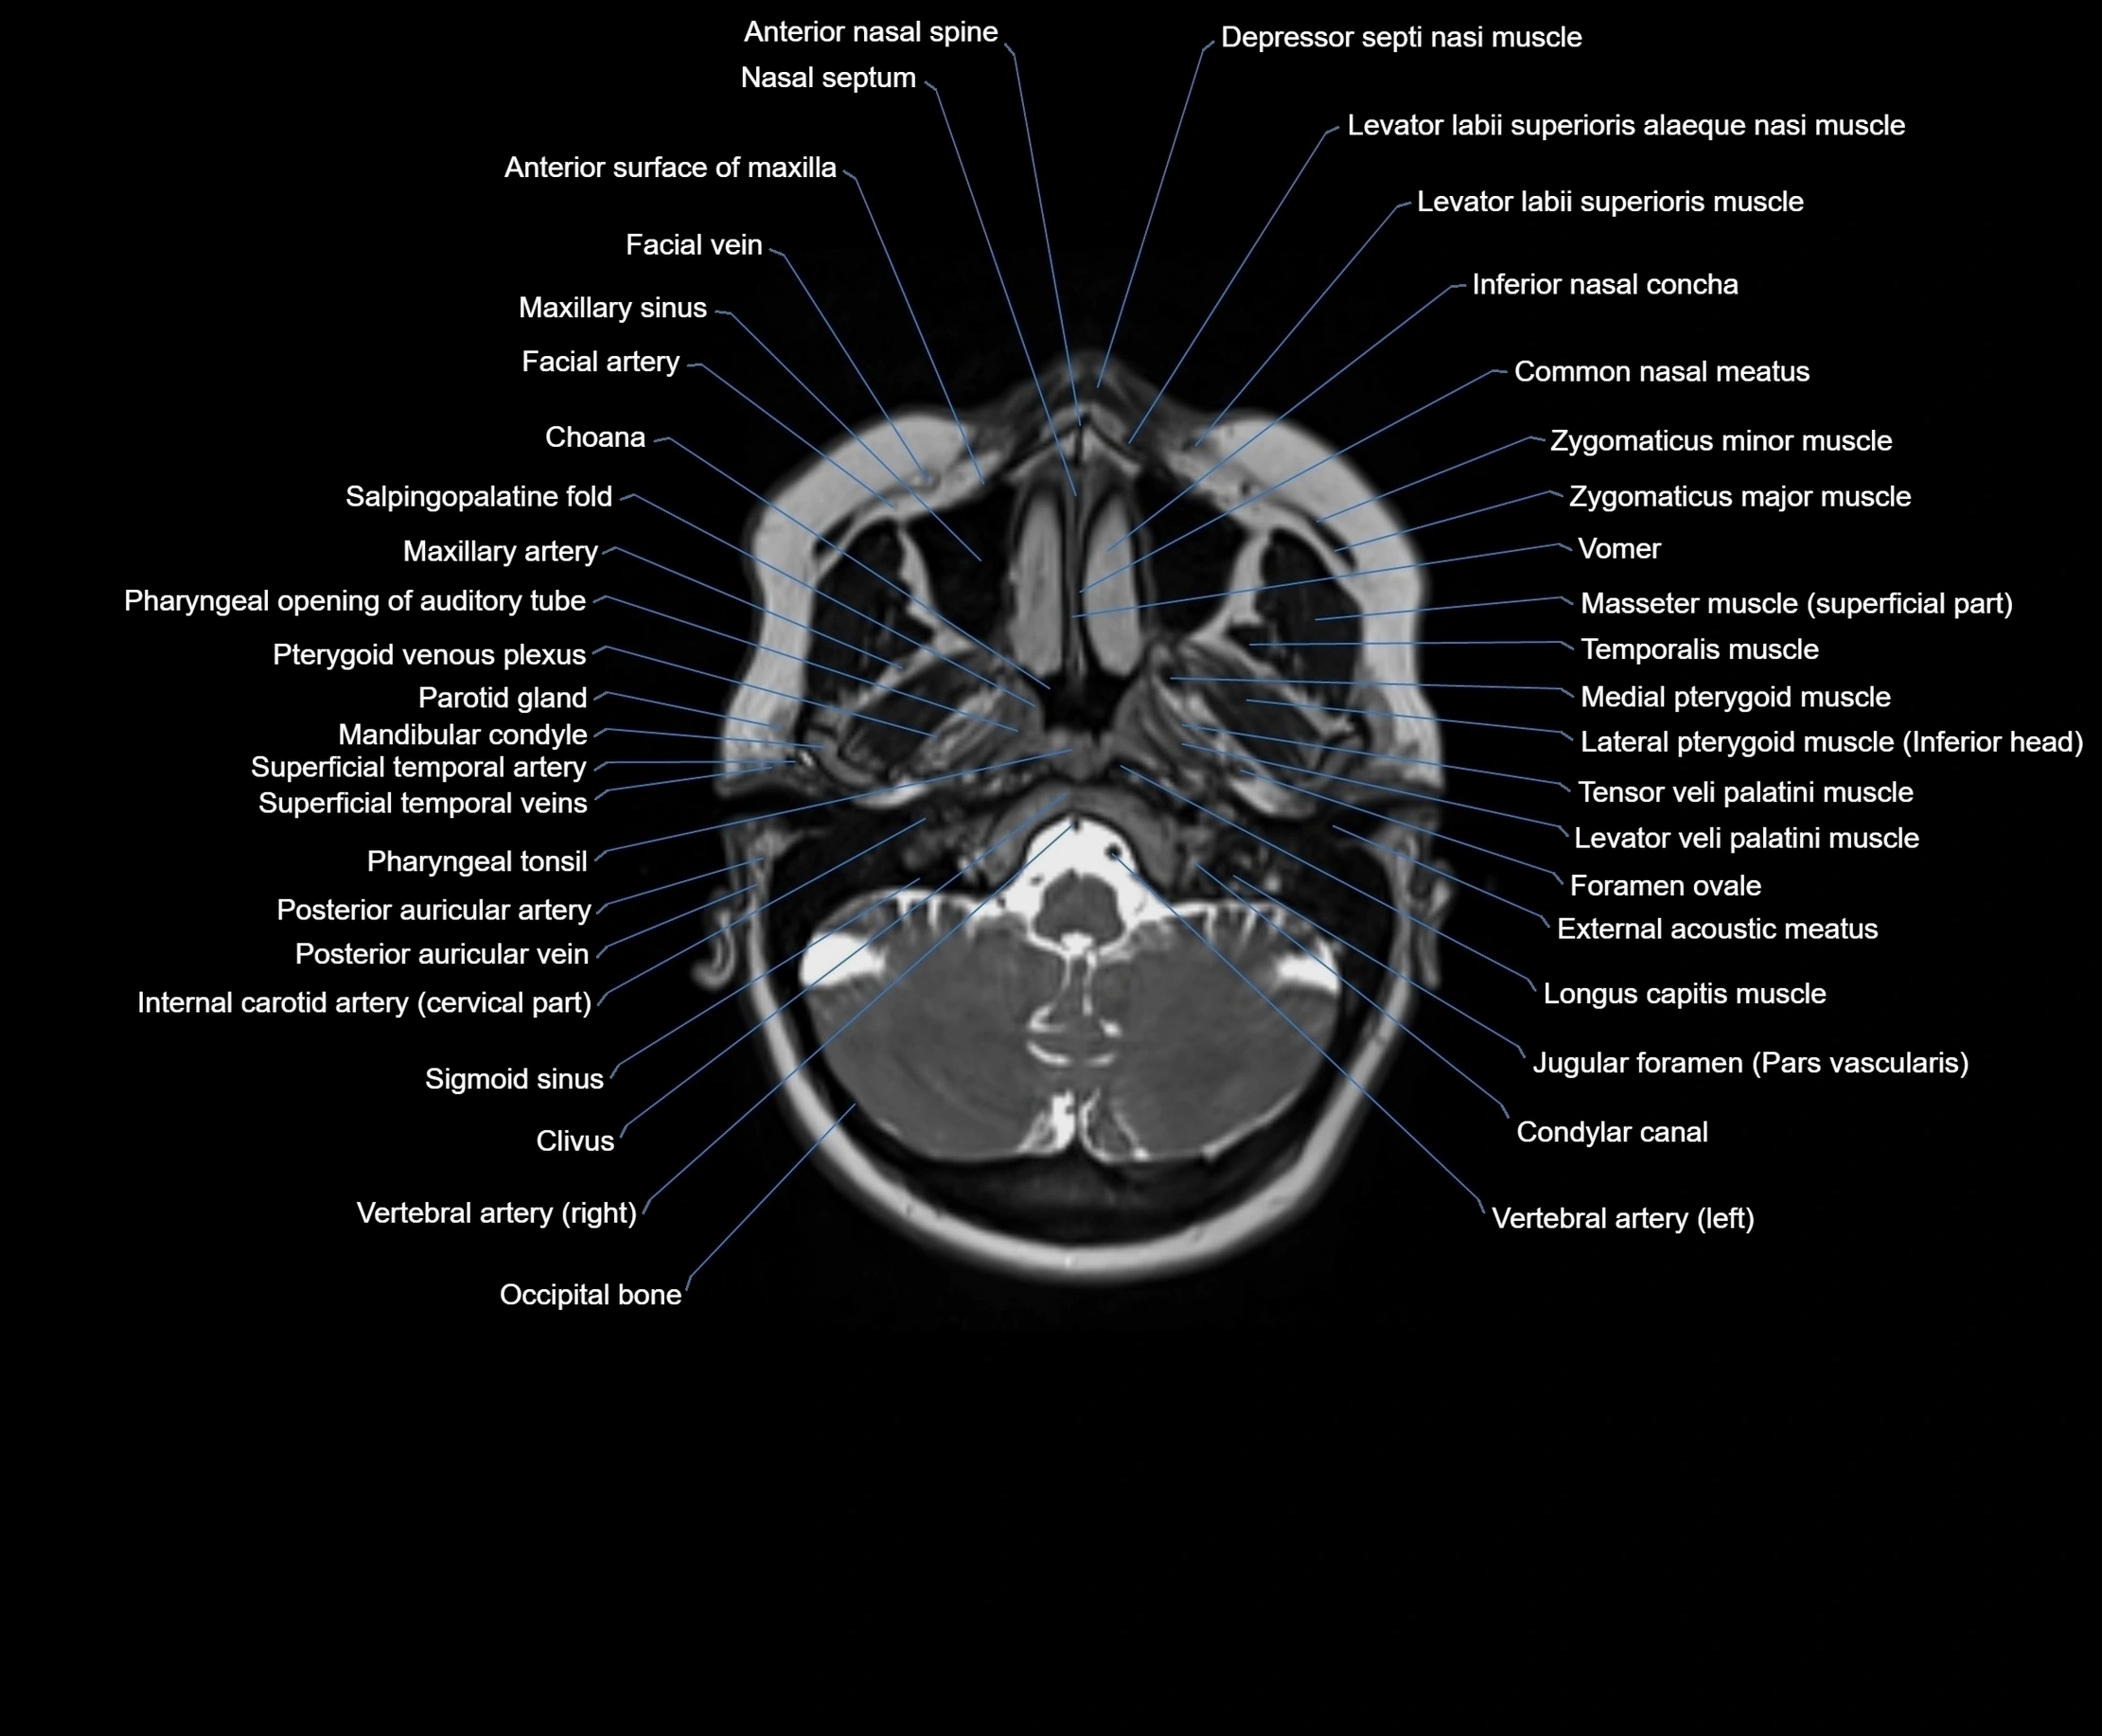

MRI images